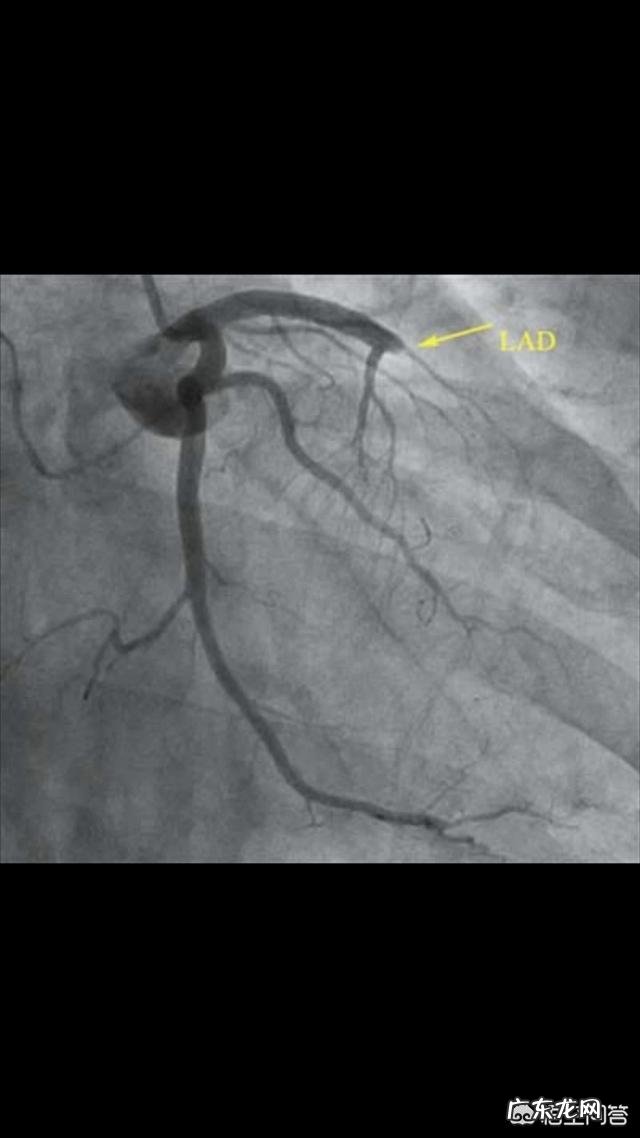

(前降支堵塞)